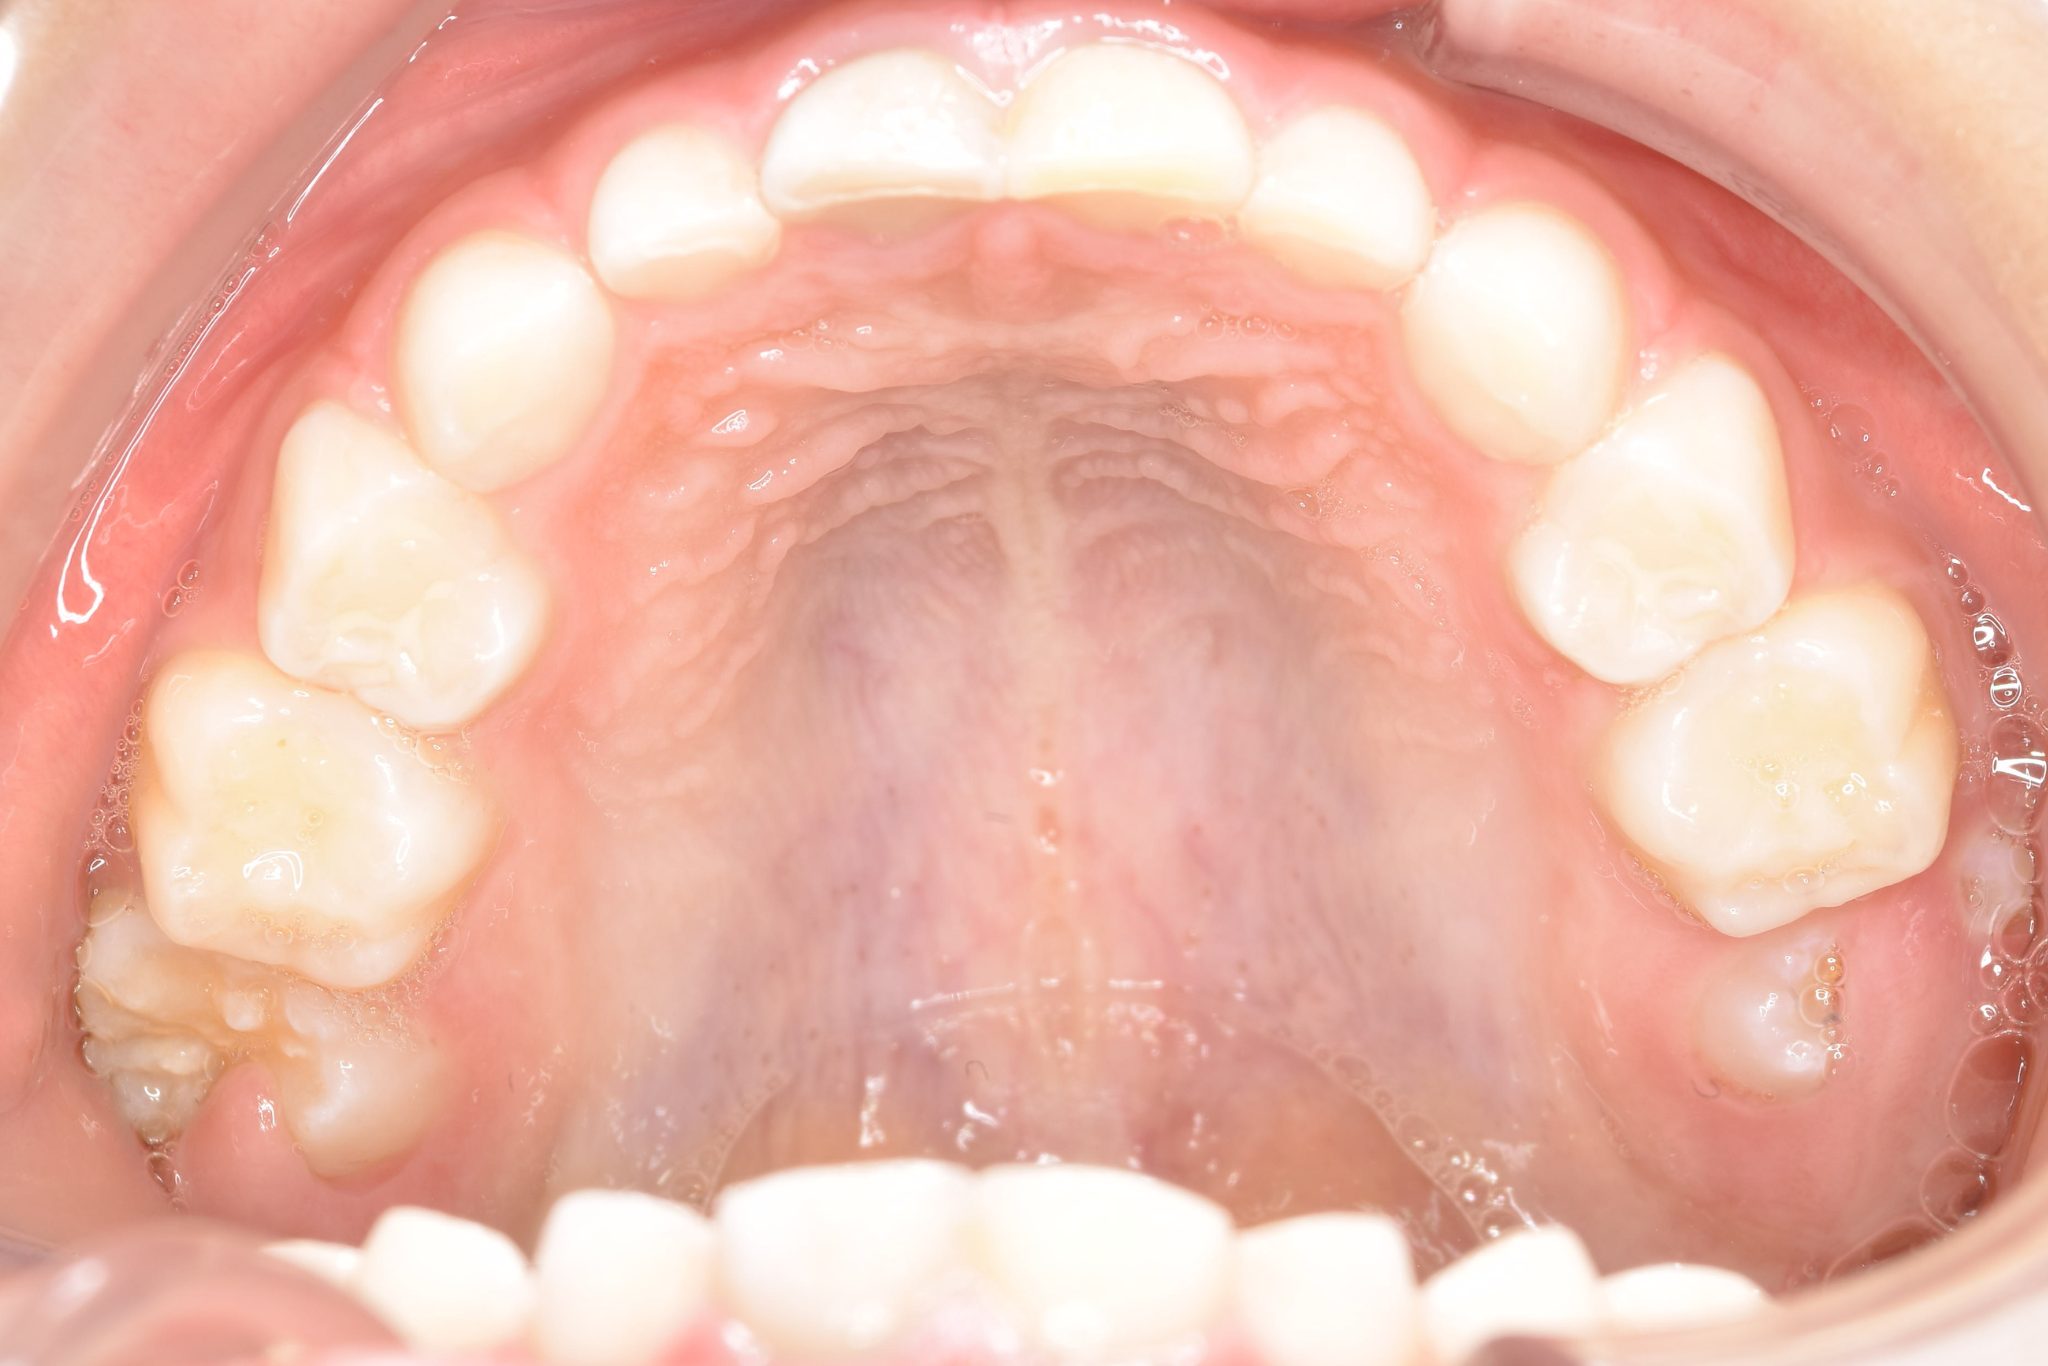

ビフォー

子どもの矯正治療|症例_121

主訴 歯並び

施術内容 上顎急速拡大装置と下顎リンガルアーチを用いて上下顎骨を拡大した。

その後マウスピース型矯正装置で歯牙を配列し良好な咬合を獲得した。

治癒期間 3年11ヶ月間